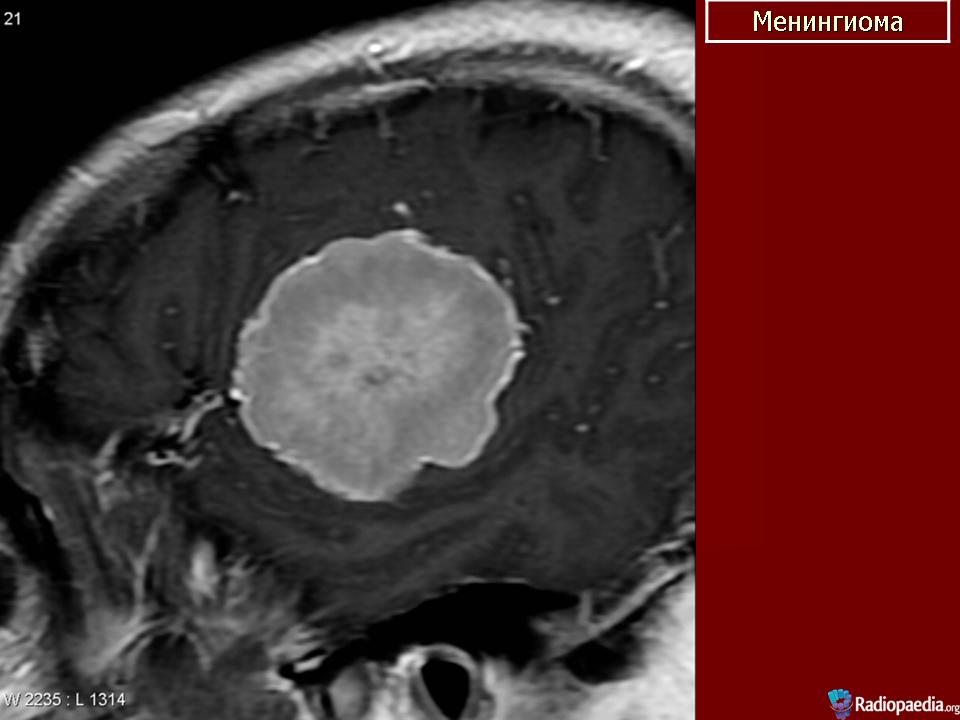

Менингиома.

Предложенный Харвеем Кушингом термин менингиомы относится к опухолям, произрастающим из твердой мозговой оболочки мозга. Менингиомы могут встречаться интракраниально или по ходу спинномозгового канала. Они произрастают из клеток Пахионовых грануляций, участвующих в резорбции ликвора.

Менингиомы обычно обнаруживаются на поверхности мозга, либо на его конвекситальной поверхности, либо на основании черепа. В редких случаях менингиомы встречаются в полости желудочков или внутрикостно. Проблема в классификации менингиом возникает из-за того, что клетки опухоли могут быть представлены клетками мезенхимы и клетками эпителия. Другие мезодермальные структуры также могут дать начало росту опухолей (например, гемангиоперицитомы или саркомы).

4. Конвекситальные менингиомы.